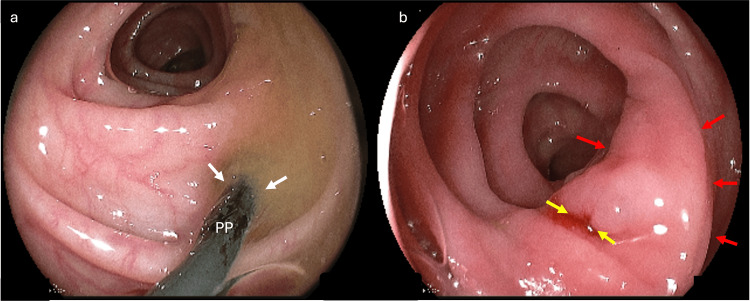

We opted for PP stent removal by colonoscopy despite the exuberant clinical setting of abdominal pain (Figure 2). The procedure was uneventful, with satisfactory patient recovery without surgical intervention. Intravenous ceftriaxone and metronidazole have been administered since her admission. She stayed in the hospital for three days after the prosthesis removal, with a good outcome and no pain complaints.